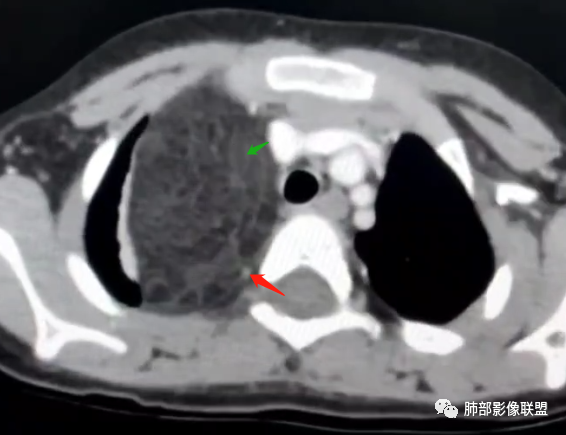

跨肺门,包绕肺血管分支,邻近肺组织受压肺不张。

可以看到造影剂进入的丛状结构

密度不均,非纯脂肪成分。斑片状密度略高区域有轻度填充式强化。

婴幼儿,病变较大,跨肺门,分叶,富含纤维或黏液、含成熟脂肪,破坏力弱或无,浸润性生长模式不明显,未见远处转移。

综合:富含成熟脂肪的、可以有丛状结构的,可以有纤维或黏液的良性或低度恶性肿瘤。常见疾病谱:脂肪瘤、神经纤维瘤样错构瘤、冬眠瘤、血管脂肪瘤、髓脂肪瘤、脂肪母细胞瘤、黏液样脂肪肉瘤。

鉴别要点:病变成分不单一,非包绕神经结构、间质血管不显著、婴幼儿,良性或低度恶性。